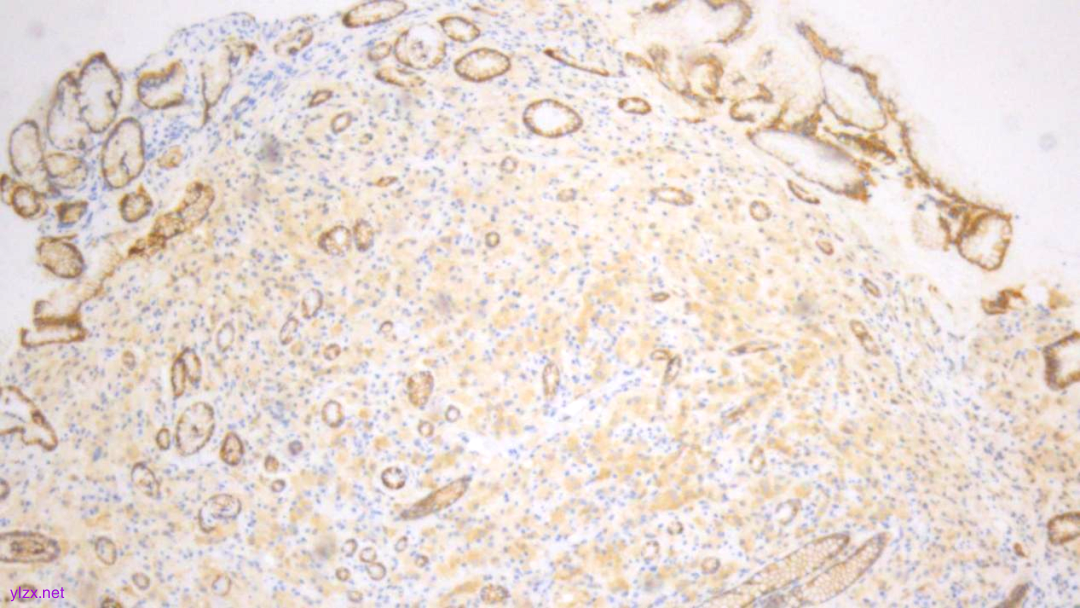

IHC结果:

P120(浆+),P16(灶+),P53(野生型表达),Her2(1+),CK7、GATA3、GCDFP-15、CK-H均(+),ER、PR、E-Cadherin、CK20均(-),Ki67(约5%+)

ER(-)

PR(-)

P120(+)

P120(部分+)

E-Cadherin(-)

GCDFP-15(弥漫+)

GATA-3(+)

CK7(弥漫强+)

Her2(1+)

Ki-67(散在+)

(宫颈2点、5点、10点活检组织及宫颈管搔刮组织)HE形态结合临床病史、免疫组化结果,符合乳腺浸润性小叶癌转移。